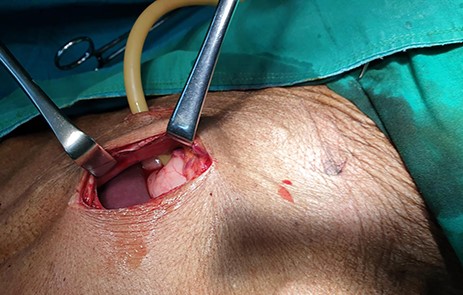

A 46-year-old female presented with progressive grade-six dysphagia, vomiting and significant unintentional weight loss. She was wasted and had a BP of 82/53 mmHg, pulse rate of 80 beats per minute, temperature of 36.4°C, saturating at 98% on room air. Her full blood picture was normal with haemoglobin of 12.3 g/dl, Creatinine 41 μmol/l, and urea was <1.0 mmol/l, sodium was 128.2 mmol/l, potassium 3.07 mmol/l. Chest X-ray was normal and the abdominal ultrasound showed no features of intra-abdominal metastasis. Oesophago-gastro-duodenoscopy (OGD) revealed a fungating tumour at 20 cm with almost complete obstruction (Fig. 1) and biopsies taken revealed oesophageal well differentiated invasive squamous cell carcinoma.

OGD showing a fungating tumour at 20 cm from the upper incisors with almost complete luminal obstruction.